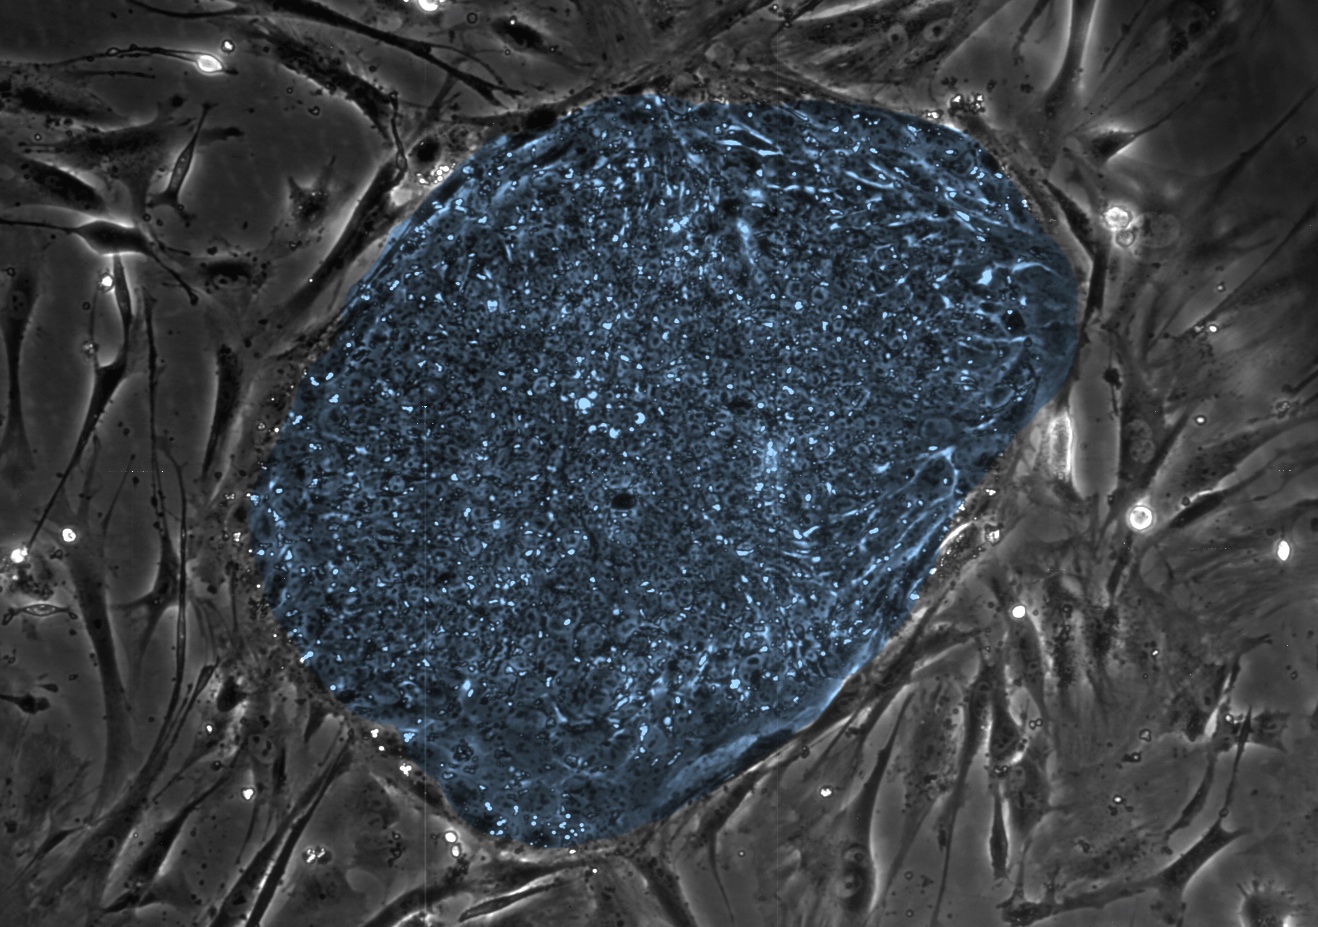

In this image, the human embryonic stem cells are colored blue. Clay Glennon, University of Wisconsin-Madison

Hey, isn’t it great that university scientists are working on making embryonic stem cell therapies? They’ve done some especially promising work in treating certain causes of blindness, including age-related macular degeneration. But now a strange but serious roadblock has come up. Because of certain federal rules, the majority of embryonic stem cell therapies being studied in universities actually aren’t eligible to become sellable treatments, the journal Cell Stem Cell reports.